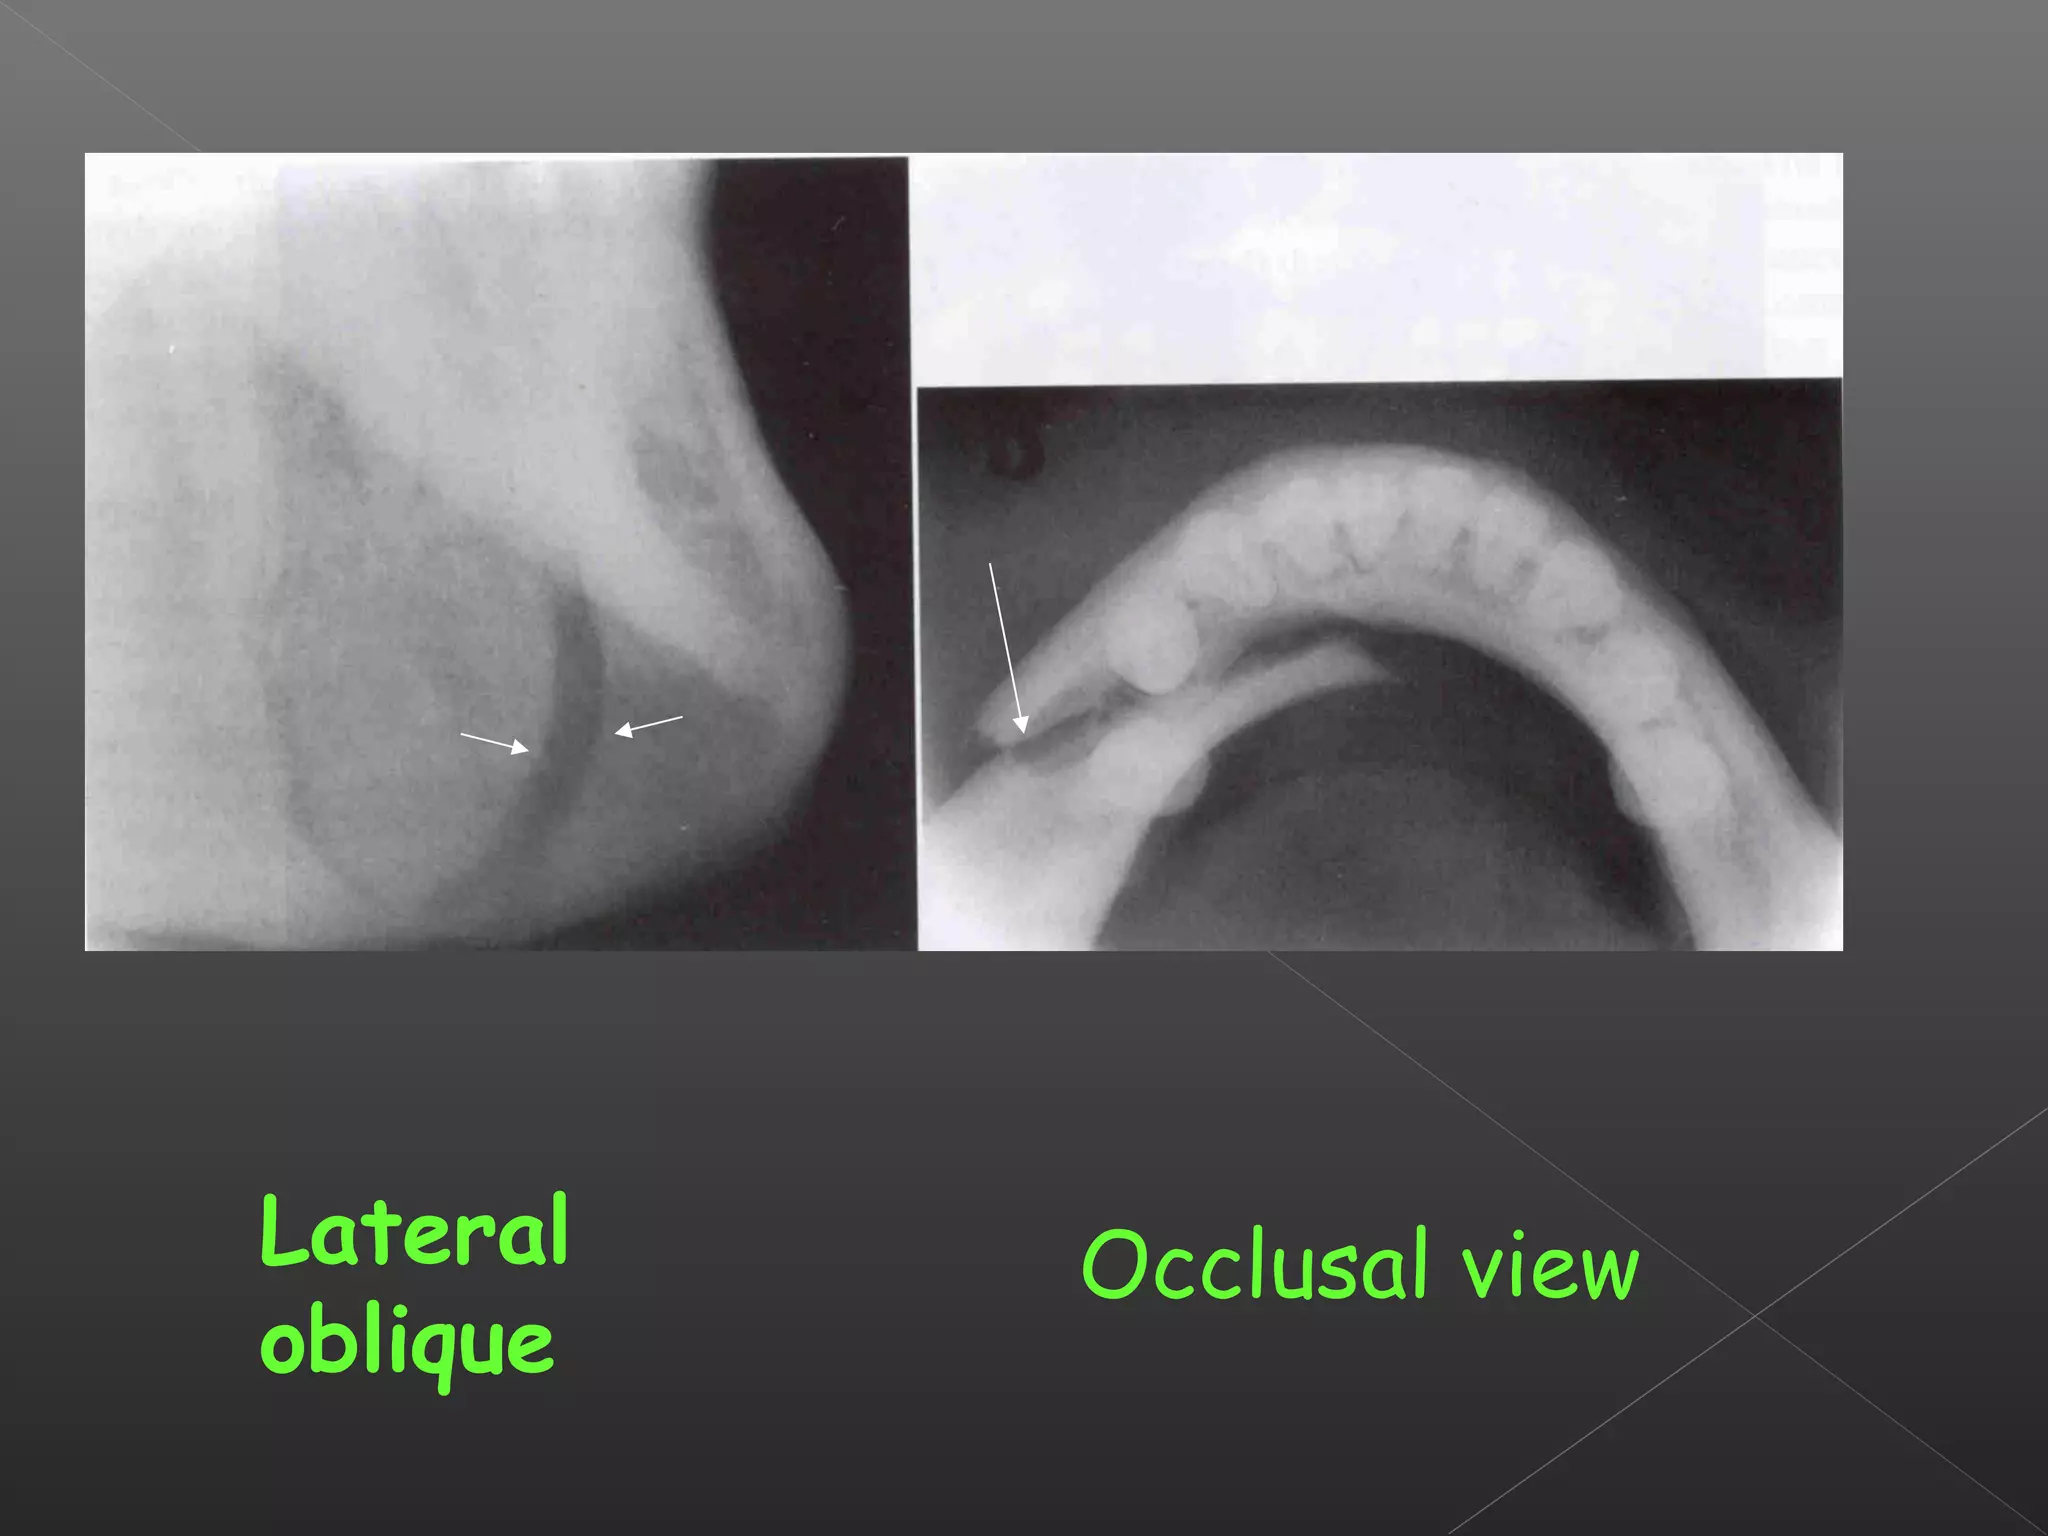

This document discusses techniques for localizing objects using radiography. It describes common reasons for needing to localize foreign bodies or other objects like unerupted teeth, fractures, or tumors. Two main techniques are described: Miller's technique which uses two radiographs at right angles, and Clark's tube-shift technique which analyzes how an object's image shifts when the projection angle is changed. The advantages and disadvantages of each technique are provided.